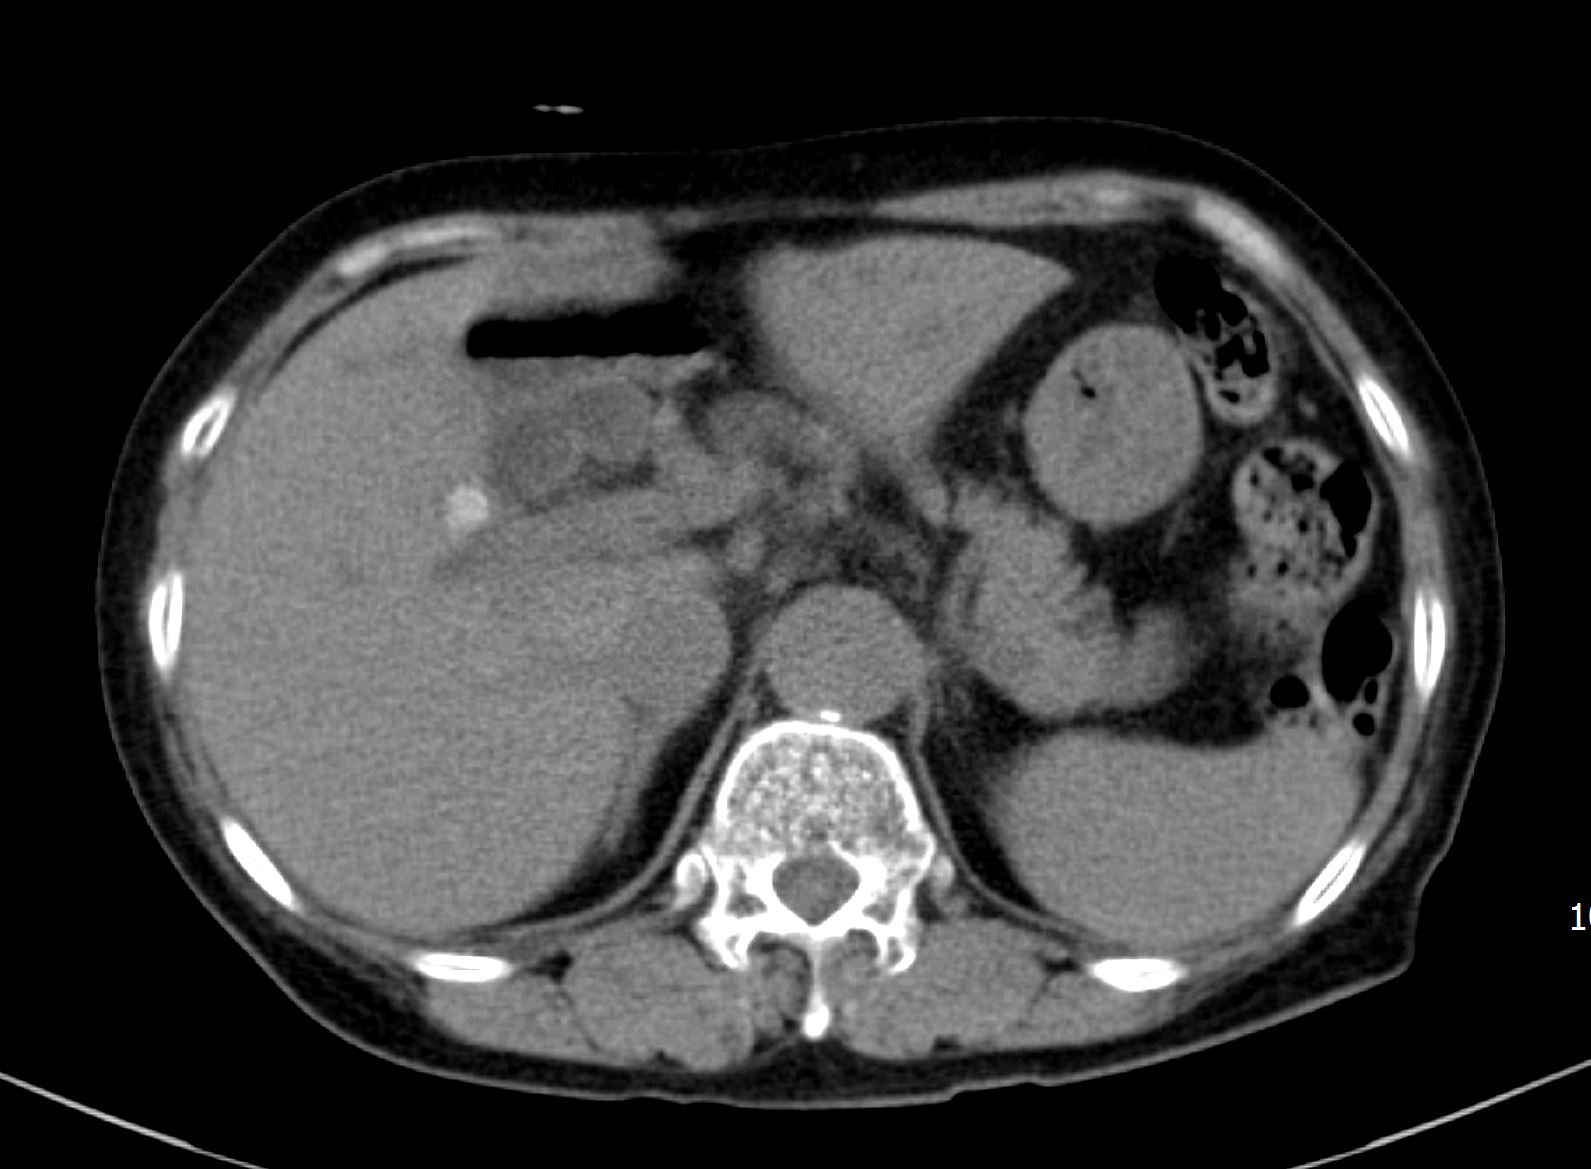

CT에서 보이던 우측 간내담관결석이 보이며, 담관의 확장이 같이 확인됩니다.

CT영상에서는 전혀 안보이던 총수담관 내 결석이 확인됩니다. 그리고, 결석 근처의 총수담관 벽이 불규칙하게 두꺼워져 보입니다.

이처럼 CT에서는 전혀 확인할 수 없었던 간외담관의 결석 및 담관암 의심소견을 초음파 영상에서는 비교적 쉽고 명확하게 확인할 수 있는 사례였습니다. 실제 담관의 확장이 있는 경우 위와 같이 CT에서는 전혀 보이지 않는 병변을 초음파영상에서 확인하는 경우가 꽤 흔합니다. 이러한 경험을 많이 하지 않은 분들이 CT의 유용성을 마치 만능에 가까운 것처럼 착각하는 경우가 있습니다만, 실제로는 이번 사례처럼 그렇지 않습니다.